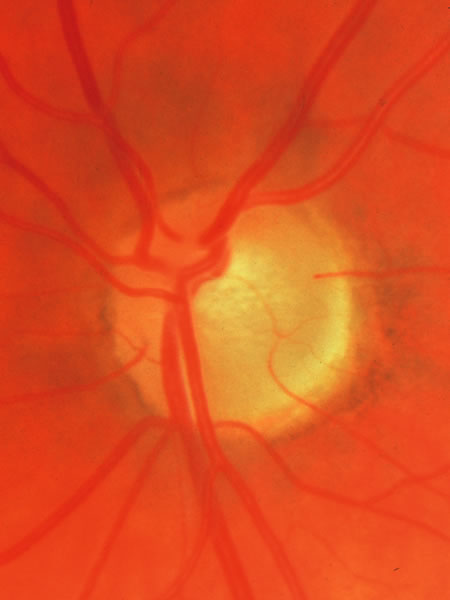

Usually all other forms of optic nerve disease (and inner retinal disease) produce simple atropy of the disc without cupping (Figs. 34 to 36), but occasional cases of cupping have been seen with anterior ischemic optic neuropathy, particularly due to giant cell arteritis (Figs. 37 and 38).

Fig. 37. Swollen optic nerve superiorly during anterior ischemic optic neuropathy caused by giant cell arteritis.

Fig. 38. Same eye after resolution of the attack, with excavation extending to the superior rim of the disc, mimicking the appearance of glaucomatous cupping.